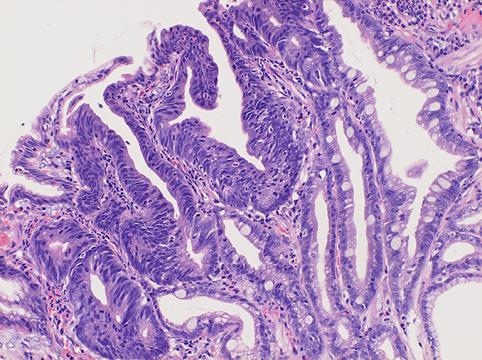

질환(병리주체)의 분류 악성 상피성종양/선암

부위(장기별) 위(부위)/전정

검사방법 마이크로

종양의 육안분류 0형(표재형)/IIc형(IIc)

종양의 최대경(밀리미터) 1~9

종양의 심달도 m